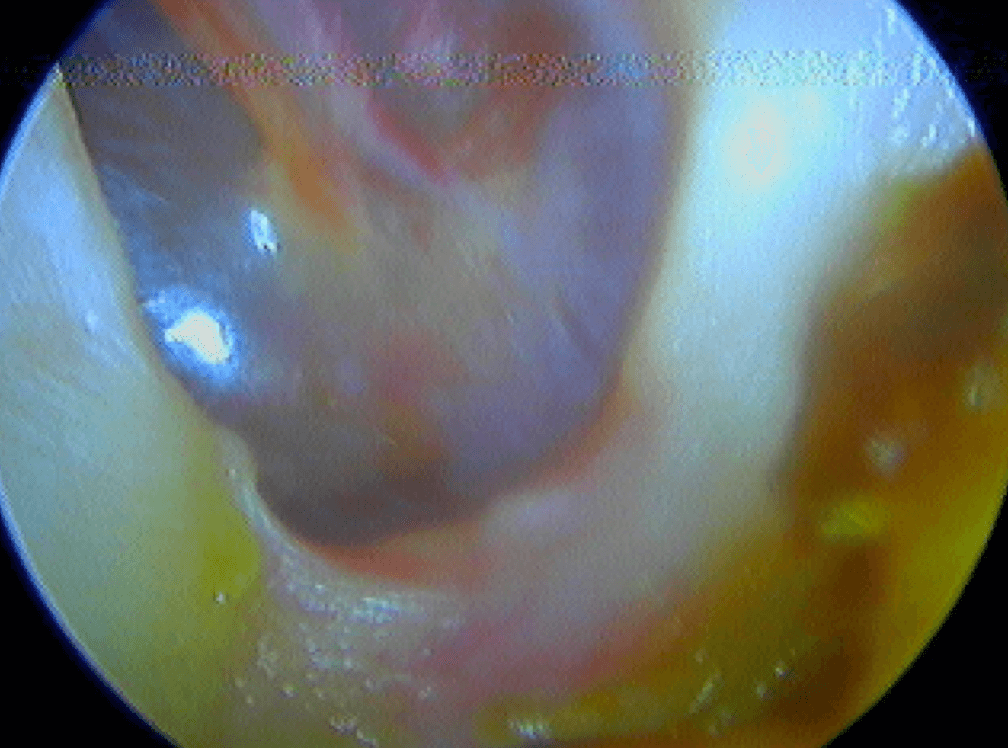

12/1 Glomus tympanique ou paragangliome tympanique

Tumeur rouge battante derrière un tympan normal, à ne pas confondre avec une otite séromuqueuse dont le liquide "bat" avec les battements des vaisseaux intratympaniques.